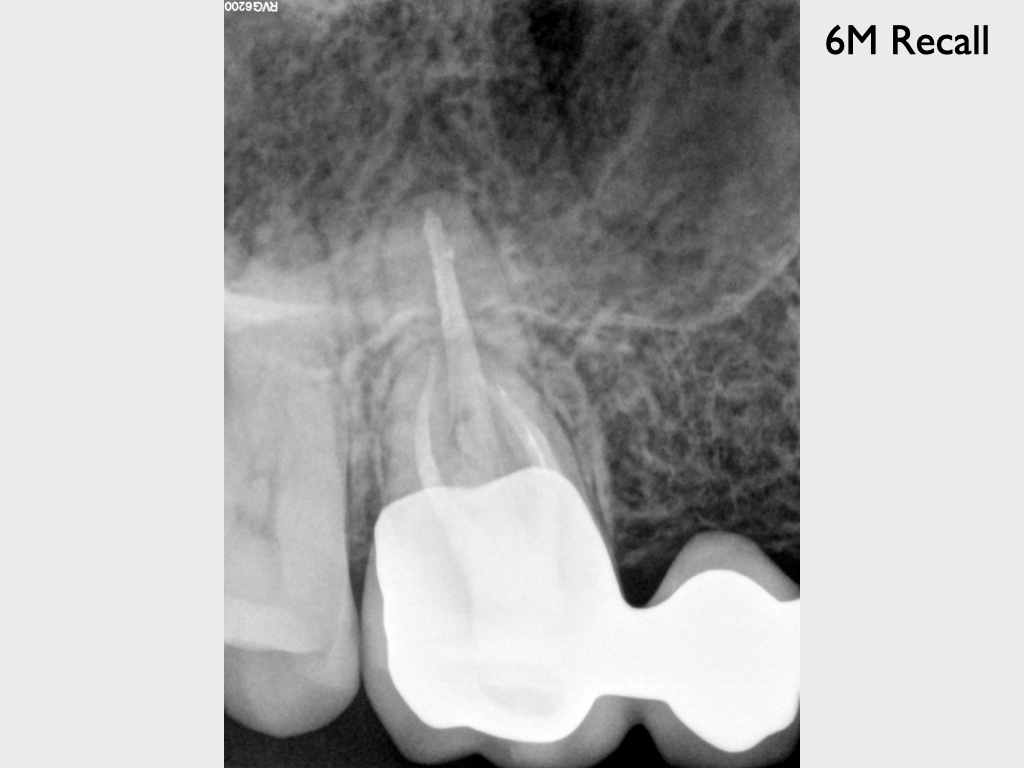

Heilung Express oder Radiodontics